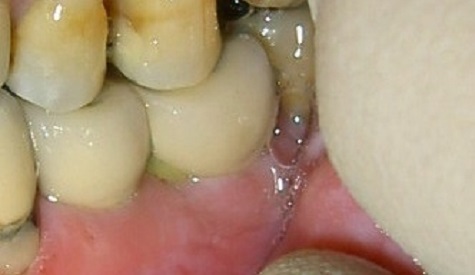

Ejemplo Implantes